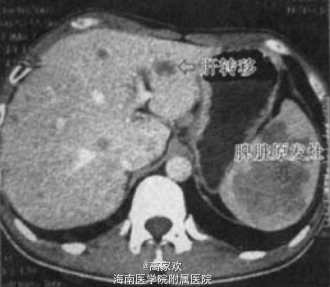

入院查体:全身浅表淋巴结未及肿大,皮肤巩膜无黄染。腹平软,无压痛,脾脏肋下2 em,质韧,轻度压痛。肝脏肋下未及。AFP、CA199、CEA、肝功能正常。 B超提示:肝脏大小、形态正常,肝内可见多发低回声占位,界清。内部回声欠均,部分呈“牛眼征”,最大位于右后叶,约11mmx8mm。脾脏大小形态饱满,被膜完整,脾实质内可见一范围约100 mmx62 mm的偏强回声占位.界清.内部回声欠均匀.CDFI示血流信号丰富。 上腹部MRI平扫+增强显示:脾脏体积增大.内部巨大肿块影。最大径约10 cm,内部信号混杂TIWI呈等低混杂信号,q'2WI呈高低混杂信号.增强扫描后呈不均匀显著强化。肝脏实质内可见多发结节影,个案报告·增强扫描后可见环形强化.最大直径约1cm。肝门、腹膜后未见明确肿大淋巴结

术前诊断:1、脾脏占位:恶性肿瘤可能;/2、肝内多发占位:转移可能。 为进一步明确诊断行诊断性脾切除术。术中见:腹腔内无明显腹水,腹腔无种植。肝脏表面可见多发结节,灰白色,质硬,最大约1cm,有一结节位于左肝外叶边缘:脾脏肿大.大小约12 cmx11cmX7 cm,包膜隆起.脾脏实质内町扪及一较大实性占位。质软。其他脏器未见明显异常.周围淋巴结未见明显肿大。行脾切除术,同时切除肝左外叶边缘处小结节送病理检查。 术后病理:脾脏血管肉瘤并肝转移。